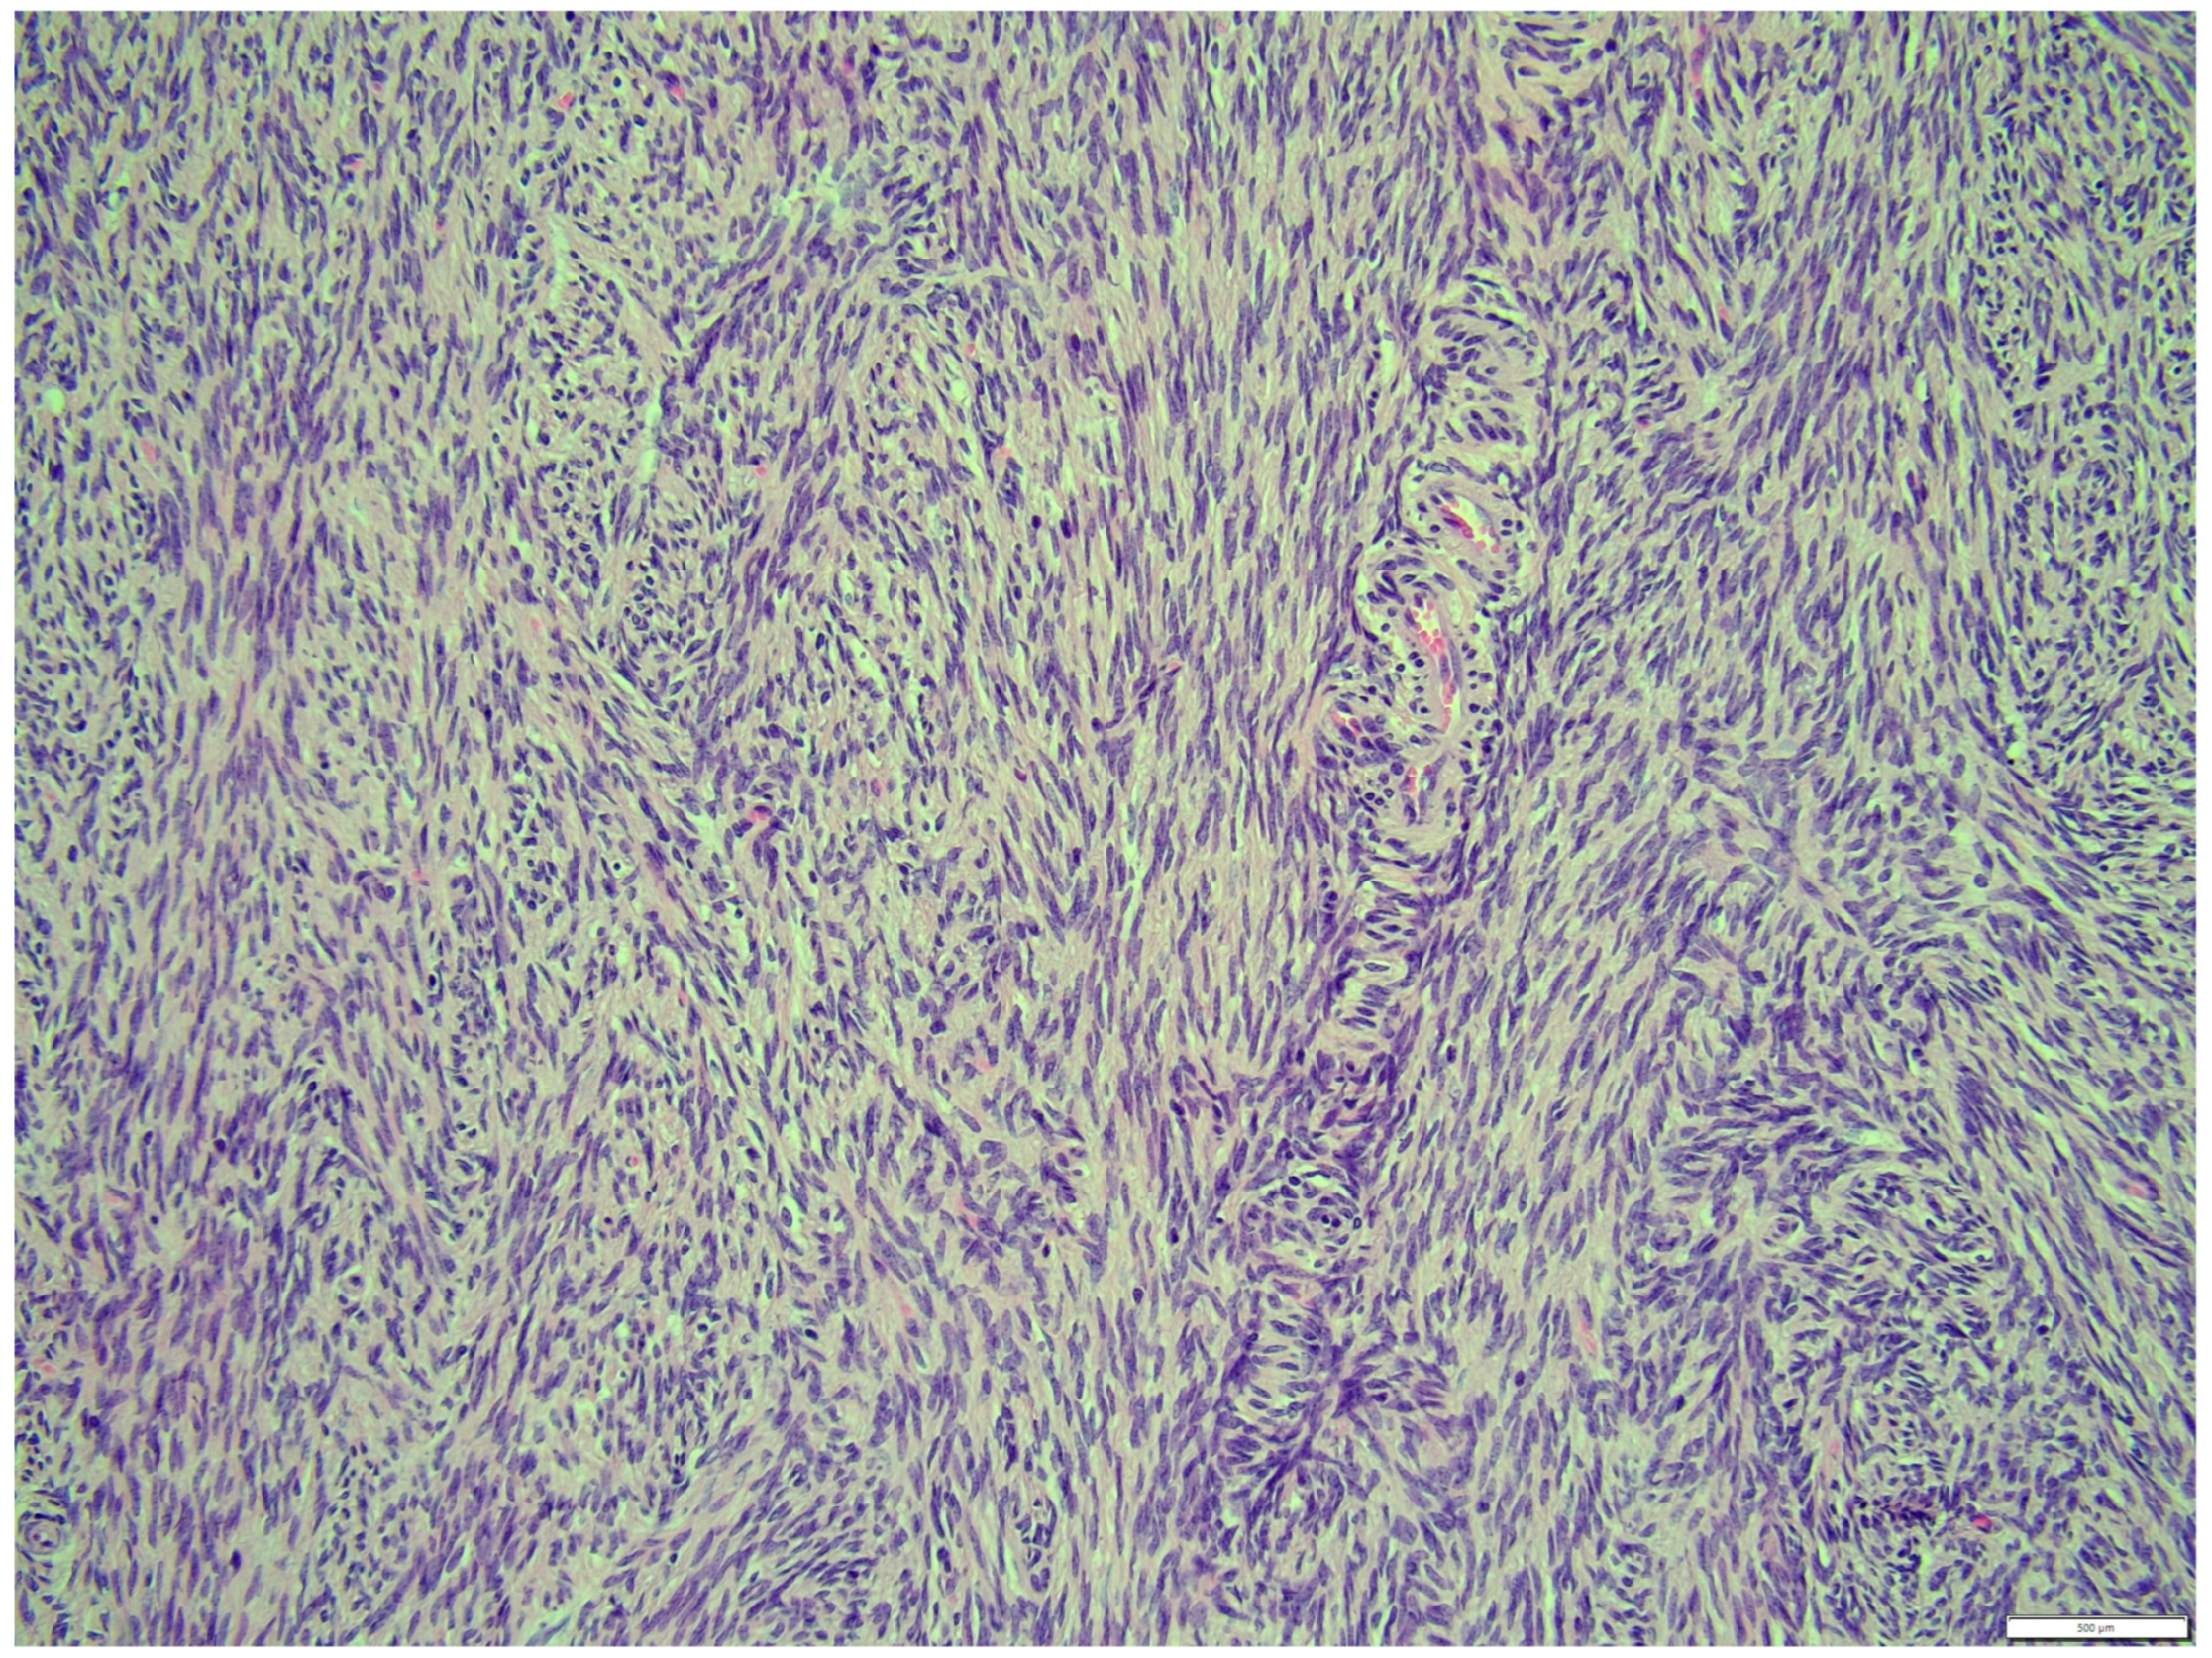

Histologically, both tumor areas were distinctly different from each other (Figure 7 and Figure 8). In the obtained sample for histological examination, the portion of the thecoma was significantly lower (Figure 9). Marked hemorrhage (but not blood-filled lacunae) and very sparse granulation-type connective tissue were observed at the border between both tumor tissues (Figure 10). Hemorrhagic blood masses infiltrated a larger part of the thecoma tissues. A single cystic structure lined with columnar epithelium was found in the hemorrhagic zone, with a very sparse amount of mucus-like material in the lumen (Figure 11).

The fibroma was composed of uniform medium-sized, spindle-shaped cells with indistinct borders and a regularly shaped and sized oval, dark or gray nucleus to long thin nucleus cells. The indistinct nucleoli and finely stippled chromatin in the nucleus were observed. The nucleus/cytoplasm ratio favored the cytoplasm. The cytoplasm was pink and long, as is common in mature spindle cells. Spindle cell anisocytosis and anisokaryosis were mild to moderate (Figure 14). Mitoses were typical. The rate of mitoses was low—2 per 10 fields at 400 magnification. The spindle-like cells were arranged in sweeping fascicles angled in a chevron-like or herringbone pattern (Figure 15). In addition, storiform areas were observed (Figure 16). The stroma had a delicate intercellular network of collagen, but a few areas of “keloid-like” sclerosis/hyalinization were found (Figure 17). The histological pattern is typical for fibrosarcoma, but not for fibroma. However, tumor cells lacked marked atypia. The ovary-derived fibroma was considered to be a pure stromal tumor of the ovary.

Figure 7. Distinction between fibroma and thecoma parts. HE, 100× magnification.

Figure 15. The spindle like cells were arranged in sweeping fascicles that are angled in a chevron-like or herringbone pattern, fibroma part. HE, 200× magnification.

Figure 16. Storiform areas, fibroma part. HE, 200× magnification.